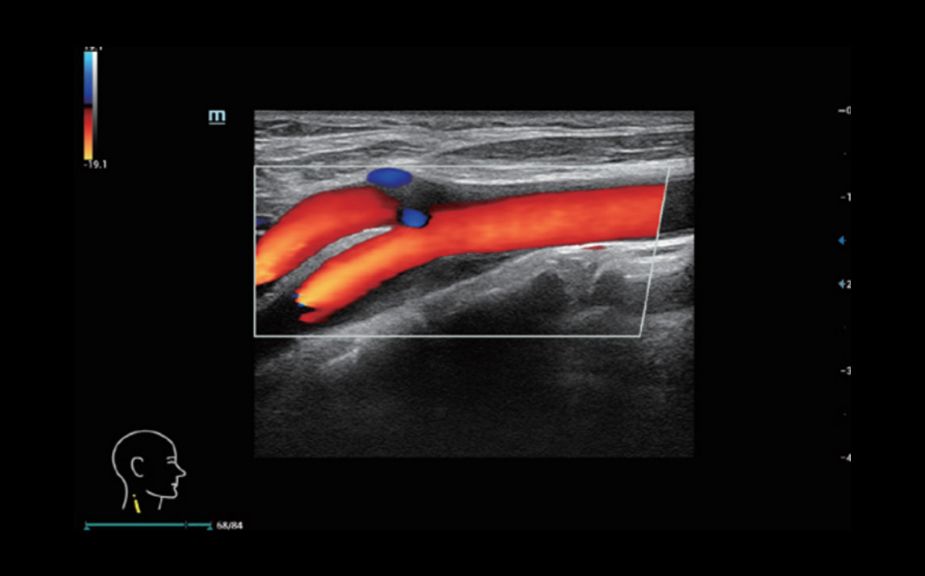

A Novel Approach of Vascular Hemodynamics: V Flow

The color coded vector arrows indicate the velocity magnitude and direction of blood cells. With an ultra-high frame rate, V Flow provides extremely vivid, accurate and angle-independent visualization of complex vascular hemodynamic profiles with comprehensive data information.

V Flow

A Novel Approach of Vascular Hemodynamics: V Flow

The color coded vector arrows indicate the velocity magnitude and direction of blood cells. With an ultra-high frame rate, V Flow provides extremely vivid, accurate and angle-independent visualization of complex vascular hemodynamic profiles with comprehensive data information.

V Flow